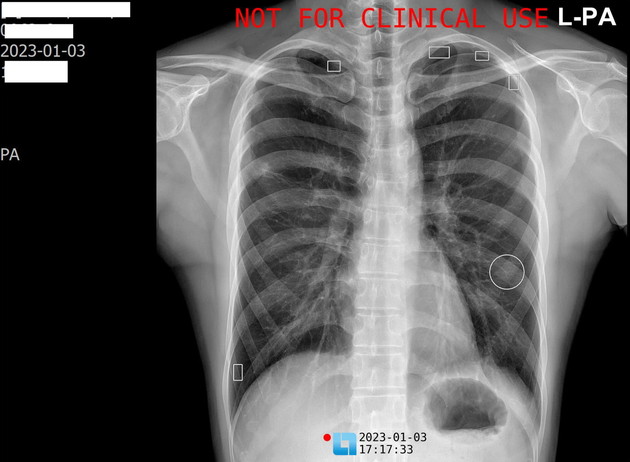

인공지능 X-ray 판독 시스템 사례

하나이비인후과병원이 새해 도입한 LuCas-CXR 시스템은 인공지능 X-ray 영상 분석 솔루션으로, 인공지능 기반 의료영상진단/분석 솔루션 업체인 모니터 코퍼레이션 (주) (대표 이경준)가 개발한 신제품이다.

LuCas-CXR은 고도의 인공지능 알고리즘과 향상된 GPU를 사용해 X-ray 영상을 2분 내에 판독할 수 있다. 이에 따라 의사가 영상 판독에 소비하는 시간을 환자 진료에 활용할 수 있게 돕는 장점이 있다.

판독의 정확도 역시 상당히 뛰어날 뿐 아니라 계속되는 인공지능 교육을 통해 더욱 향상될 전망이다. 내과 전문의의 육안 판독과 함께 중복 활용할 경우 만에 하나 발생할 수 있는 의사의 판독 오류도 예방할 수 있다.

하나이비인후과병원은 LuCas-CXR을 이용해 환자들의 기관지와 폐 관련 질환을 보다 빠르고 정확하게 진단해 더욱 효과적인 치료를 할 수 있을 것으로 기대하고 있다.